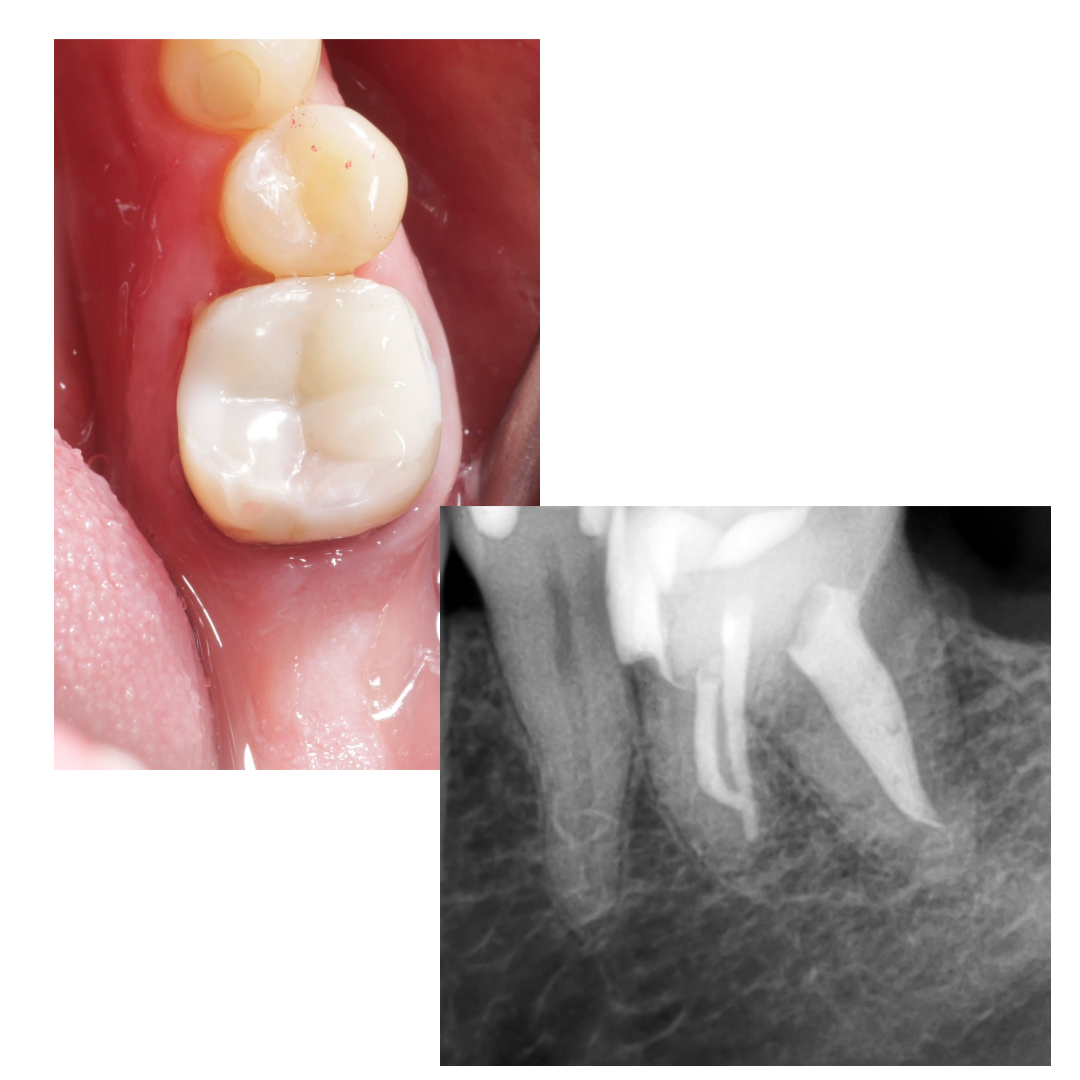

🔹Почистил, отпесочил, понял что можно восстановить. Но из-за инвагинации стенки, решил вот так заморочиться с клином (воткнуть вертикально и зафиксировать)

🔹Щечную и язычную стенку доделал фрихендом. На следующий визит, распломбировка цемента и перепломбировка : биокерамика + непрерывная волна

П.с: ортопеду не показывал ещё, так как план минимум был собрать из пломбы. Как думаете можно в этой ситуации сделать хорошую коронку?